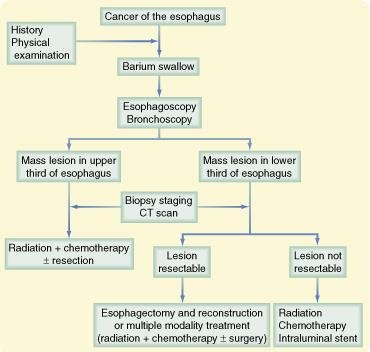

Apesar das várias modalidades de exames de imagem (radiografia, exame contrastado com bário, tomografia computadorizada e tomografia por emissão de pósitrons) auxiliarem a determinar a presença e a extensão da doença, o diagnóstico de câncer esofágico é baseado na biopsia esofágica.

Uma vez estabelecido histologicamente o diagnóstico de carcinoma de esôfago após esofagoscopia e biopsia, o próximo passo é o estadiamento para determinar qual a opção terapêutica mais apropriada.

O estádio do tumor é classificado mais frequentemente conforme o sistema proposto pela American Joint Committee on Câncer (AJCC). Este sistema é baseado no TNM, onde "T" (tumor) indica o grau de invasão progressivo (de 1 a 4) do tumor na parede do esófago. O "N" é o envolvimento linfonodal, e "M* representa as metástases a distância.

A condição do tumor primário (T) é definida pela profundidade da invasão tumoral. A condição ganglionar (N) é definida pela ausência (N0) ou presença (N±) de metástases regionais. HGD = displasia de alto grau

O estadiamento adequado é importante porque a sobrevida está intimamente relacionada ao estádio de T e N, e com a avaliação de invasão do tronco celíaco. Cânceres T4, que não se beneficiam com a operação, podem ser adequadamente avaliados por USE. Sobrevida de 5 anos, conforme estádios:

- I (50% a 94%),

- II (15% a 65%),

- III (6% a 23%),

- IV (< 5%), apesar de alguns relatos de sobrevida em estádio IV de até 27%